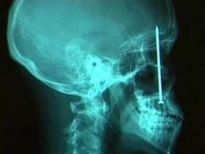

Şoke eden röntgen filmleri

Bu röntgen filmleri görenleri şaşkına çeviriyor!